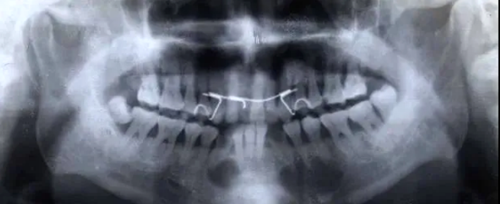

各類根尖周病的X片表現(xiàn)

(1) 致密性骨炎

臨床表現(xiàn):好發(fā)于年青人,常見下頜第一磨牙,常有大齲壞,無(wú)癥狀。

X線表現(xiàn):骨小粱增粗、變密,骨髓腔變窄、消失;

硬化區(qū)與正常組織無(wú)明顯分界;

牙周膜間隙增寬,根尖無(wú)增粗。